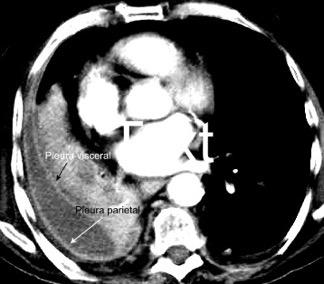

Signo de la Pleura separada “Split pleural sign”

Capas pleurales de grosor uniforme realzadas por el contraste

No específico de empiema. Indica “exudado”. 68% de pacientes con empiema pleural.

Capas pleurales de grosor uniforme

Realce grasa extrapleural (30%)

> Grasa Extrapleural. (60-80%)

Kraus GJ. Split pleural sign. Radiology 2007